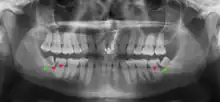

Impacted wisdom teeth are classified by their direction of impaction, their depth compared to the biting surface of adjacent teeth and the amount of the tooth's crown that extends through gum tissue or bone. Impacted wisdom teeth can also be classified by the presence or absence of symptoms and disease. Screening for the presence of wisdom teeth often begins in late adolescence when a partially developed tooth may become impacted. Screening commonly includes a clinical examination as well as x-rays such as panoramic radiographs.

Impacted wisdom teeth are classified by the direction and depth of impaction, the amount of available space for tooth eruption, and the amount of soft tissue or bone (or both) that covers them. The classification structure helps clinicians estimate the risks for impaction, infections and complications associated with wisdom teeth removal.[6] Wisdom teeth are also classified by the presence (or absence) of symptoms and disease.[7]

Impacted wisdom teeth are often described by the direction of their impaction (forward tilting, or mesioangular being the most common), the depth of impaction and the age of the patient as well as other factors such as pre-existing infection or the presence of pathology (cysts, tumors or other disease).[5]: 143–144 Each of these factors is used to predict the difficulty (and rate of complications) when removing an impacted tooth, with age being the most reliable predictor[8] rather than the orientation of the impaction.[9]

Another classification system often taught in U.S. dental schools is known as Pell and Gregory Classification. This system includes a horizontal and vertical component to classify the location of third molars (predominately applicable to lower third molars): the third molar's relationship to the level of the teeth already in the mouth, being the vertical or x-component and to the anterior border of the ramus being the horizontal or y-component.[10]

If the tooth cannot be assessed with clinical exam alone, the diagnosis is made using either a panoramic radiograph or cone-beam CT. Where unerupted wisdom teeth still have eruption potential several predictors are used to determine the chance of the teeth becoming impacted. The ratio of space between the tooth crown length and the amount of space available, the angle of the teeth compared to the other teeth are the two most commonly used predictors, with the space ratio being the most accurate. Despite the capacity for movement into early adulthood, the likelihood that the tooth will become impacted can be predicted when the ratio of space available to the length of the crown of the tooth is under 1.[5]: 141

There is no standard to screen for wisdom teeth. It has been suggested, absent evidence to support routinely retaining or removing wisdom teeth, that evaluation with panoramic radiograph, starting between the ages of 16 and 25 be completed every 3 years. Once there is the possibility of the teeth developing disease, then a discussion about the operative risks versus long-term risk of retention with an oral and maxillofacial surgeon or other clinician trained to evaluate wisdom teeth is recommended. These recommendations are based on expert opinion level evidence.[19] Screening at a younger age may be required if the second molars (the "12-year molars") fail to erupt as ectopic positioning of the wisdom teeth can prevent their eruption. Radiographs can be avoided if the majority of the tooth is visible in the mouth.